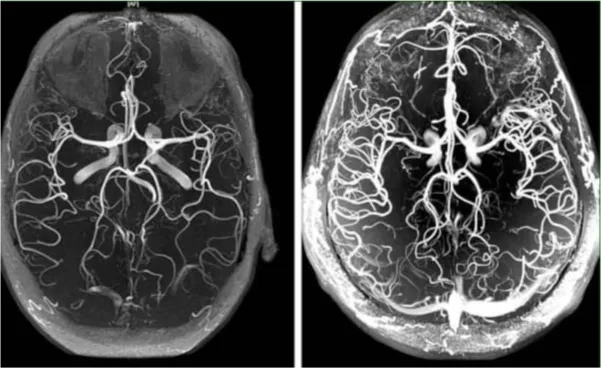

Visaptis Caps შეიცავს კონცენტრირებულ მცენარეულ ექსტრაქტებს, რომლებიც აღადგენს ვიზუალური აპარატის ფუნქციონირებას, ასუფთავებს თვალის სისხლძარღვებს, ამცირებს თვალშიდა წნევას და აღადგენს მხედველობის სიმახვილეს.

ამ ინსტრუმენტის მთავარი ამოცანაა ახალი ქსოვილის შექმნა თვალების დაზიანებული და აღდგენილი სისხლის მიწოდების ნაცვლად.

„Visaptis Caps“ ერთი კურსი საკმარისია 930 000-ზე მეტი უჯრედის გასააქტიურებლად, რომლებიც უშუალოდ მონაწილეობენ მხედველობის აღდგენის პროცესში. და ასე ყოველ ჯერზე. ეს არის ახალი მეთოდის მთავარი პრინციპი.

ყველა ეს დაავადება თვალის სისხლძარღვების დარღვევის შედეგია. მაგრამ ადამიანების უმეტესობა აგრძელებს ტანჯვას და იყენებს უსარგებლო წვეთებს ან ტაბლეტებს, სიმპტომების აღმოფხვრის იმედით.

«Visaptis Caps» იცავს სისხლძარღვებს. აუმჯობესებს სისხლის მიმოქცევას და ასტაბილურებს მხედველობას